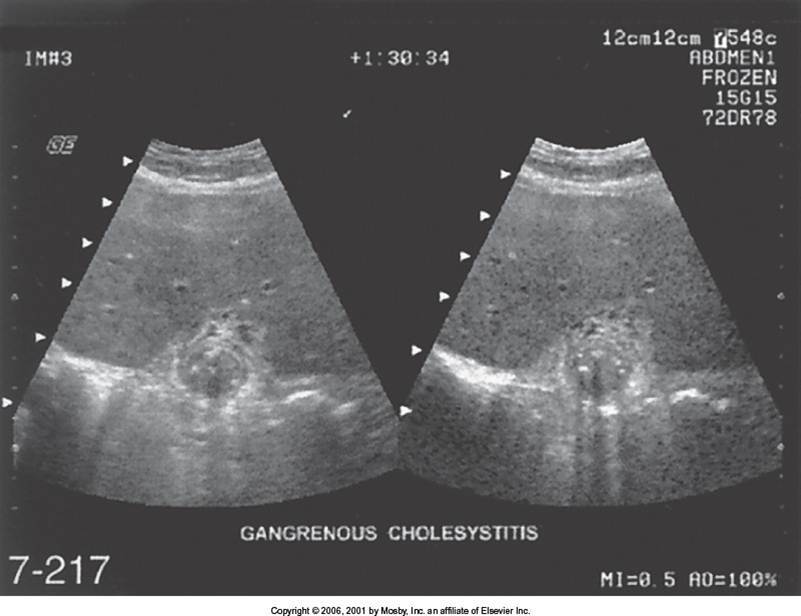

Gangrenous Cholecystitis